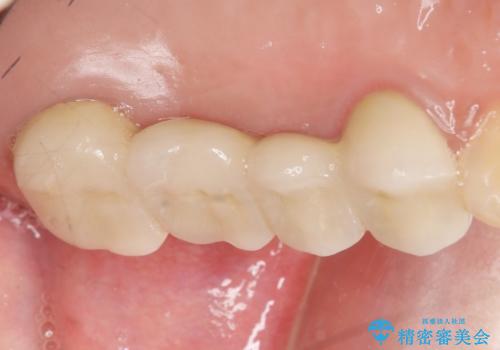

奥歯で咬むことができるようになり、また見た目も自然だと大変喜んで頂けました。

上顎骨がかなり薄くインプラント治療に対し望ましい状態でないことからも、自家歯牙移植は有意義であったと考えます。

被せ物の種類:メタルボンドクラウン エコノミー フルベイク